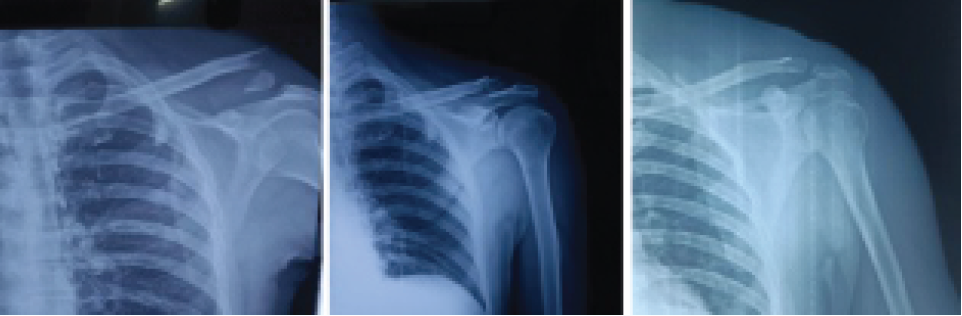

All patients had fracture union in a mean of 15 weeks (Figs. 3a, b, c).

Figure 3: (a) X-ray showing Neers type 2 lateral end clavicle fracture. (b) X-ray showing 2 month post endobutton fixation. (c) X-ray showing 6-month post endobutton fixation.